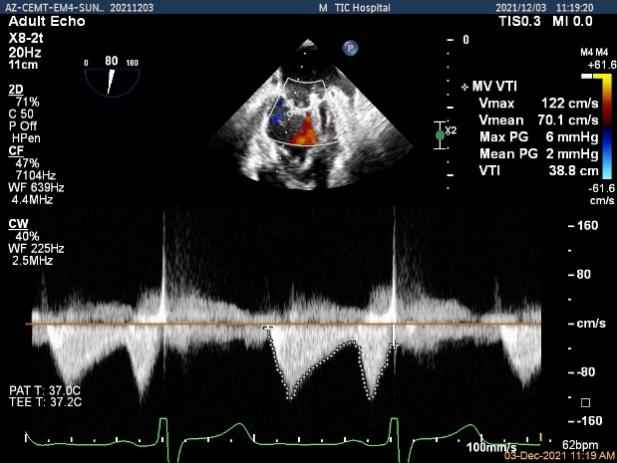

二尖瓣口平均跨瓣压差:2mmHg